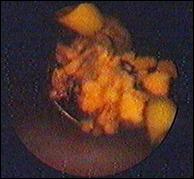

b). Fir de nylon intravezical

Figura 62. Nod din fir de nylon.